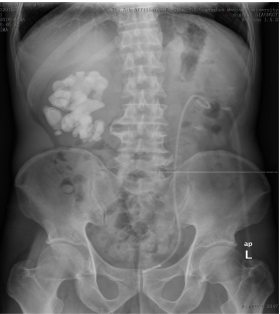

看一看这疯狂的石头,几乎把双肾有的空间都占满了,特别是右肾(图片左侧)。而这石头的拥有者——患者李先生和家属四处投医无果后,最后慕名来到泌尿外科就诊。泌尿外科专家经过一番研究讨论后,决定先使用经皮肾镜行左侧经皮肾碎石取石术,为左边肾脏进行结石清除。术后,再次为李先生进行x光检查,结果显示:左边结石已基本清除。